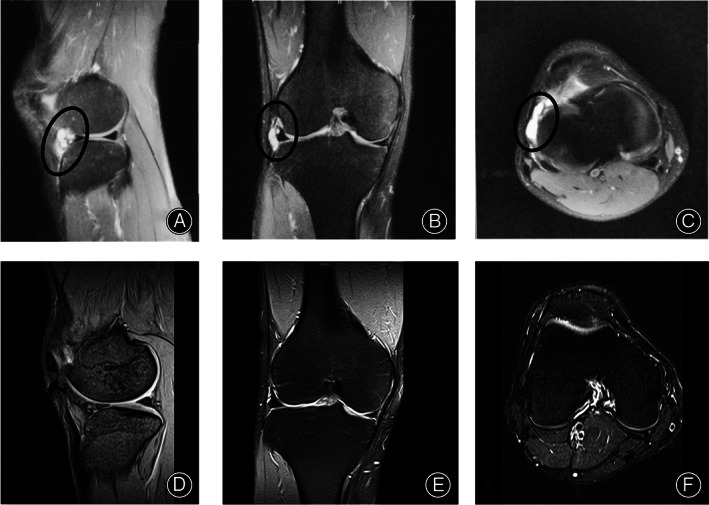

Radiological Assessment

There were parameniscal cysts that occurred with a meniscal tear in all patients preoperatively. Radiological imaging was consistent with the patients' symptoms and all patients were eligible for the operation. As for the postoperative imaging in the modified excision group, they showed this new method removed the cysts, retained the synovial margin of the meniscus without making destruction of the internal structure of meniscus, and enabled the stability of the structure. The case is shown in Figure 6.

FIG. 6.

A 32‐year‐old male who felt pain over the lateral aspect of right knee with parameniscal cysts. (A–C) Sagittal, coronal and axial T2‐weighted fat‐saturated images demonstrated cysts. (D–F) Sagittal, coronal and axial T2‐weighted fat‐saturated images demonstrated the removal of cyst.